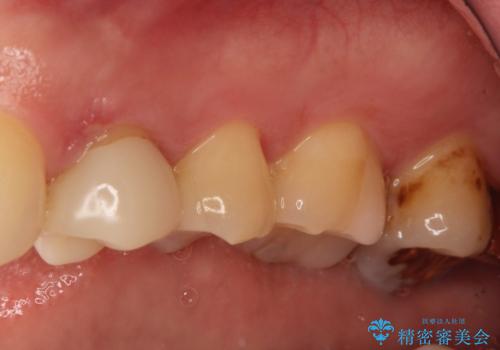

- 定期健診にて虫歯が見つかった患者さんです。他院で保険治療(CR、プラスチック)したところとまだ処置されていないところが虫歯になっていました。

セラミックインレーで治療しました。

以前保険治療で治したところが再び虫歯になっていました。保険治療で使用される材料は主にプラスチックなので必ず劣化がおきます。再治療のリスクを減らすために、セラッミックインレーで治療を行いました。セラミックインレーには劣化がほとんどありません。当院ではシリコンで型取りを行っているので、適合が良い被せものが出来き再治療のリスクを減らすことが出来ます。